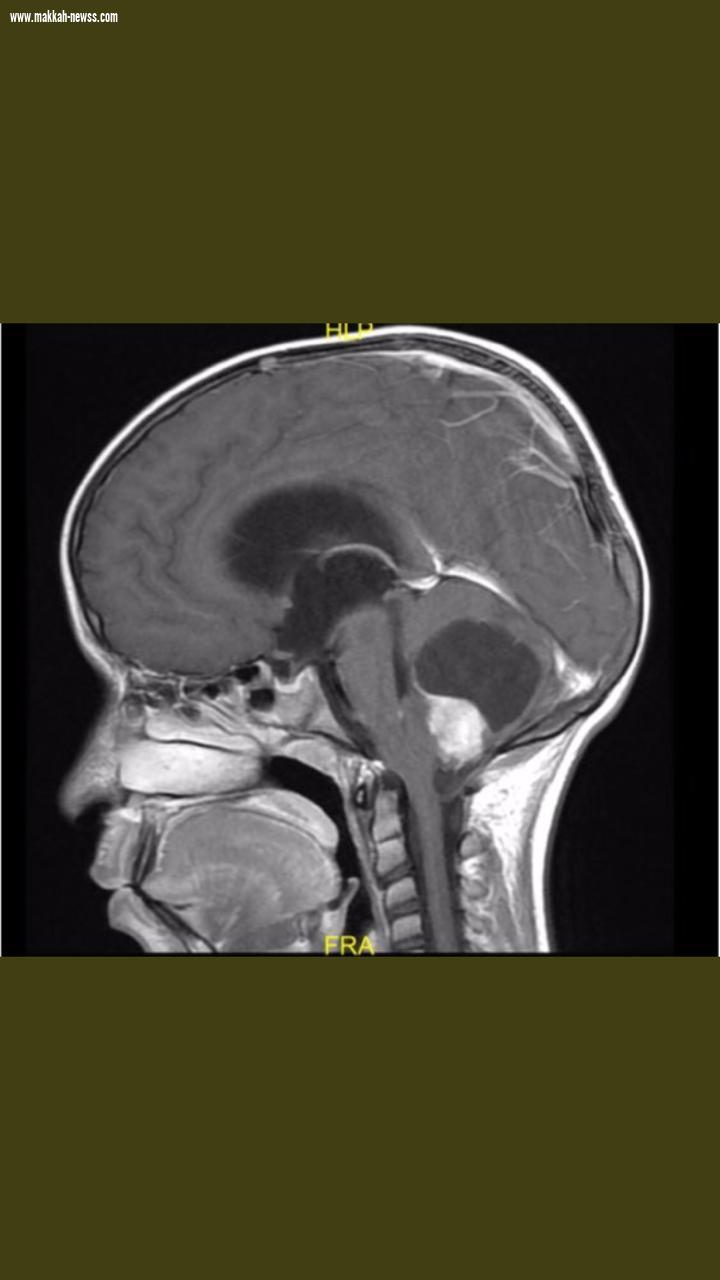

فايزة عسيري صحيفة صوت مكة حقق الأطباء الإستشاريون بقسم جراحة المخ و الأعصاب بمستشفى شرق جدة نجاحاً كبيراً بفضل الله و عنايته تمثل في إعادة طفل بعمر سبع سنوات لممارسة حياته الطبيعية و من ثم عودته إلى مقاعد الدراسة لمواصلة تعليمه مع أقرانه و زملائه بعد أن تم نقله بسبب معاناته المستمرة من صداع و عدم توازن في المشي و تم الكشف عليه من قبل الاطباء ، أظهرت نتيجة أشعة الرنين المغناطيسي للدماغ وجود ورم بالمخيخ يبلغ حجمه 5×4×4 سم مع وجود ضغط كبير على جذع الدماغ ، و حاجته إلى التدخل السريع لإنقاذ الطفل بإجراء عملية جراحية على مرحلتين كانت الأولى بصفة عاجلة عن طريق المنظار لمعالجة الإستسقاء الحاد في الدماغ فيما تمثلت العملية الجراحية الثانية في الإستئصال المباشر و الكامل للورم وقد تمت هاتان العمليتان بنجاح كامل بتوفيق الله . و أمضى المريض بعدهما أسبوعاً كاملاً بقسم العناية المركزة و كانت حالته مستقرة و في تحسن سريع ولله الحمد قرر بعدها الأطباء المعالجون للمريض خروجه من المستشفى بعد تحسن حالته و غادر إلى منزله لممارسة حياته الطبيعية وهو في حالة ممتازة و بدون أي مضاعفات و لله الحمد و حالياً على مقاعد الدراسة .